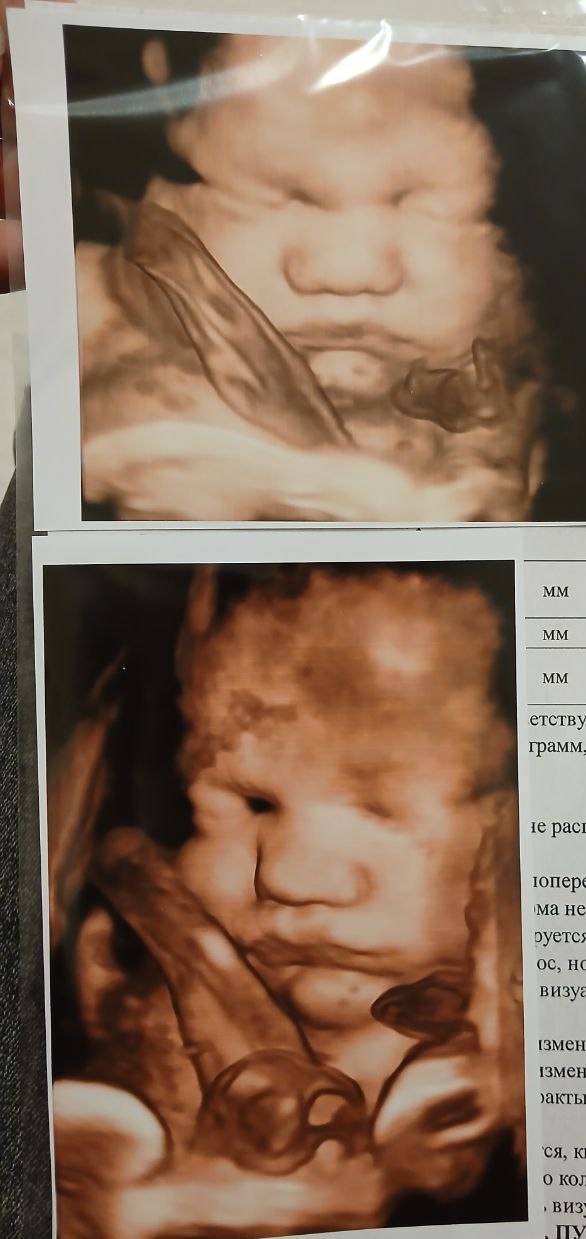

Щёчки малыша: радость материнства и уход за кожей

Ну каковы щёчки уже! 🩷